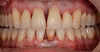

Une patiente de 32 ans présente une tendance à la maladie parodontale et un décalage important entre les dents du haut (maxillaires) et les dents du bas (mandibulaires). La patiente se plaint de l’esthétique de son sourire. De plus, plusieurs incisives présentent des mobilités. Un traitement parodontal ultrasonique est mené.

Une préparation orthodontique est ensuite conduite par le Dr Charles GRAINDORGE pour permettre une chirurgie orthognatique afin de rétablir une occlusion (rencontre) satisfaisante entre les dents du haut et celles du bas.

Deux attelles métalliques sont posées en haut et en bas pour conserver les résultats du traitement orthodontique. Le métal derrière les dents génère un ombrage disgracieux et l’esthétique du sourire est décevante.